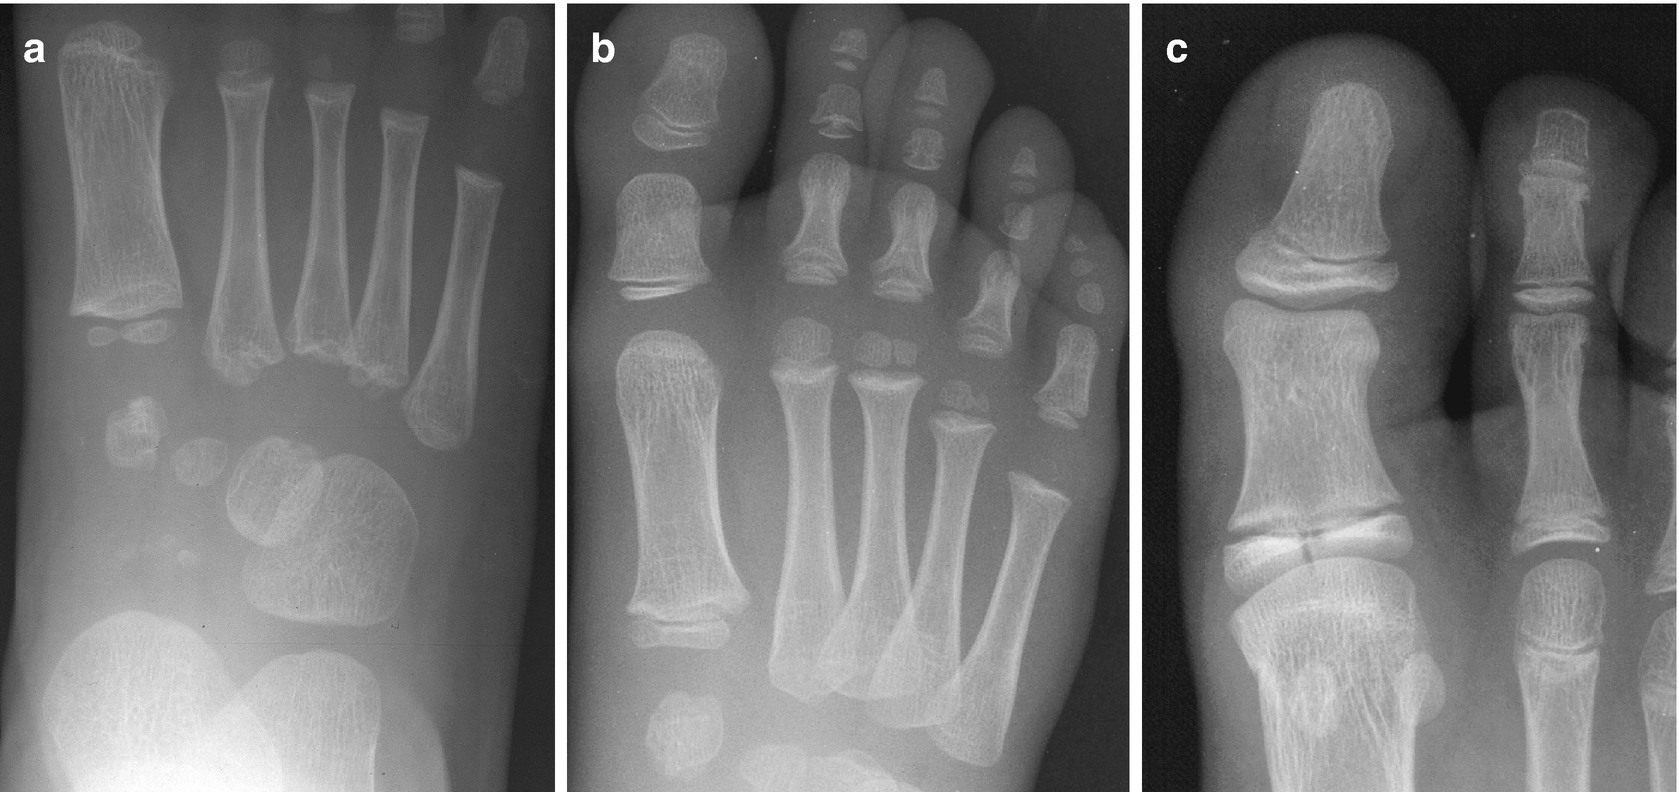

17+ Anatomy Of Foot Xray. To find the abnormal one must have an idea of normal. How to read xray of the ankle?

Sagittal cross section of the ankle and foot based on mri showing ankle joint, and tendos (calcaneal tendo, tibialis anterior, extensor hallucis. Xray medial oblique foot anatomy. To find the abnormal one must have an idea of normal. Remember to check the whole film, though.